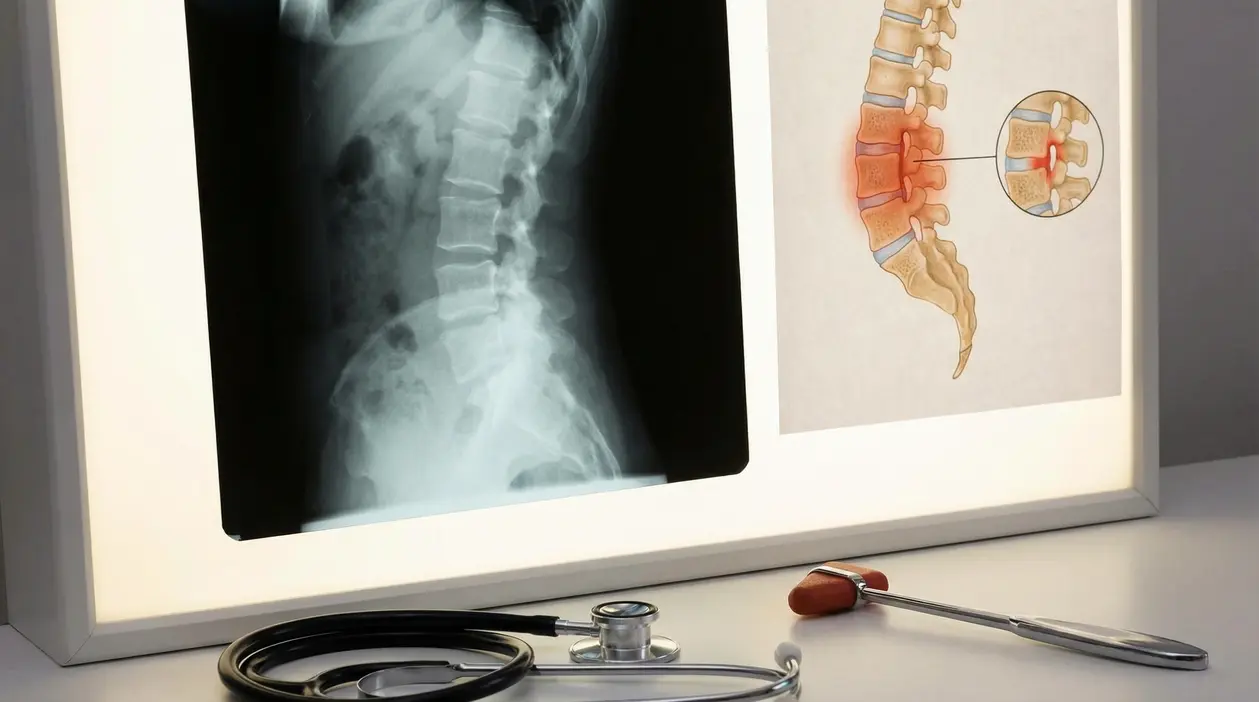

- radiografia del bacino, utile per vedere alterazioni delle sacro iliache

- risonanza magnetica, spesso preziosa nelle fasi iniziali perché mostra l’infiammazione prima dei danni strutturali